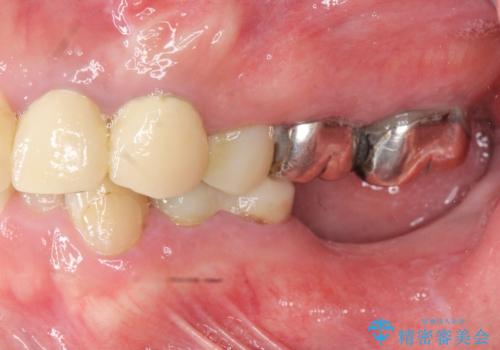

- 「虫歯が多発し、治療が終わらない。歯も無くなったし今後悪くならないような治療をしたい。」と精密治療を希望され来院されました。

虫歯の徹底的な除去やセラミック補綴、精密根管治療、歯周外科を行うことで、治療後に歯磨きがしやすく、かみやすい機能的な仕上がりへと導きます。